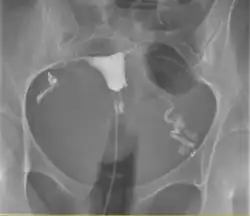

![]() A normal hysterosalpingogram. Note the catheter entering at the bottom of the screen, and the contrast medium filling the uterine cavity (small triangle in the center). | |

Hysterosalpingography (HSG), also known as uterosalpingography,[1] is a radiologic procedure to investigate the shape of the uterine cavity and the shape and patency of the fallopian tubes. It is a special x-ray procedure using dye to look at the womb (uterus) and fallopian tubes.[2] In this procedure, a radio-opaque material is injected into the cervical canal, and radiographs are taken. A normal result shows the filling of the uterine cavity and the bilateral filling of the fallopian tube with the injection material. To demonstrate tubal patency, spillage of the material into the peritoneal cavity needs to be observed. Hysterosalpingography has vital role in treatment of infertility, especially in the case of fallopian tube blockage.

The procedure involves x-rays (fluoroscopy).[7] Images are taken to demonstrate the filling of endometrial cavity, which shows full view of the fallopian tubes demonstrating the spillage of contrast material into peritoneum, the extent of the block if no spillage is present, or a delayed view in the case of abnormal cavities (locule) within. Subject may have vaginal spotting for one to two days, accompanied with pain that may persist for up to two weeks. Some medical centres routinely give prophylactic antibiotics before subject is allowed home.[3]